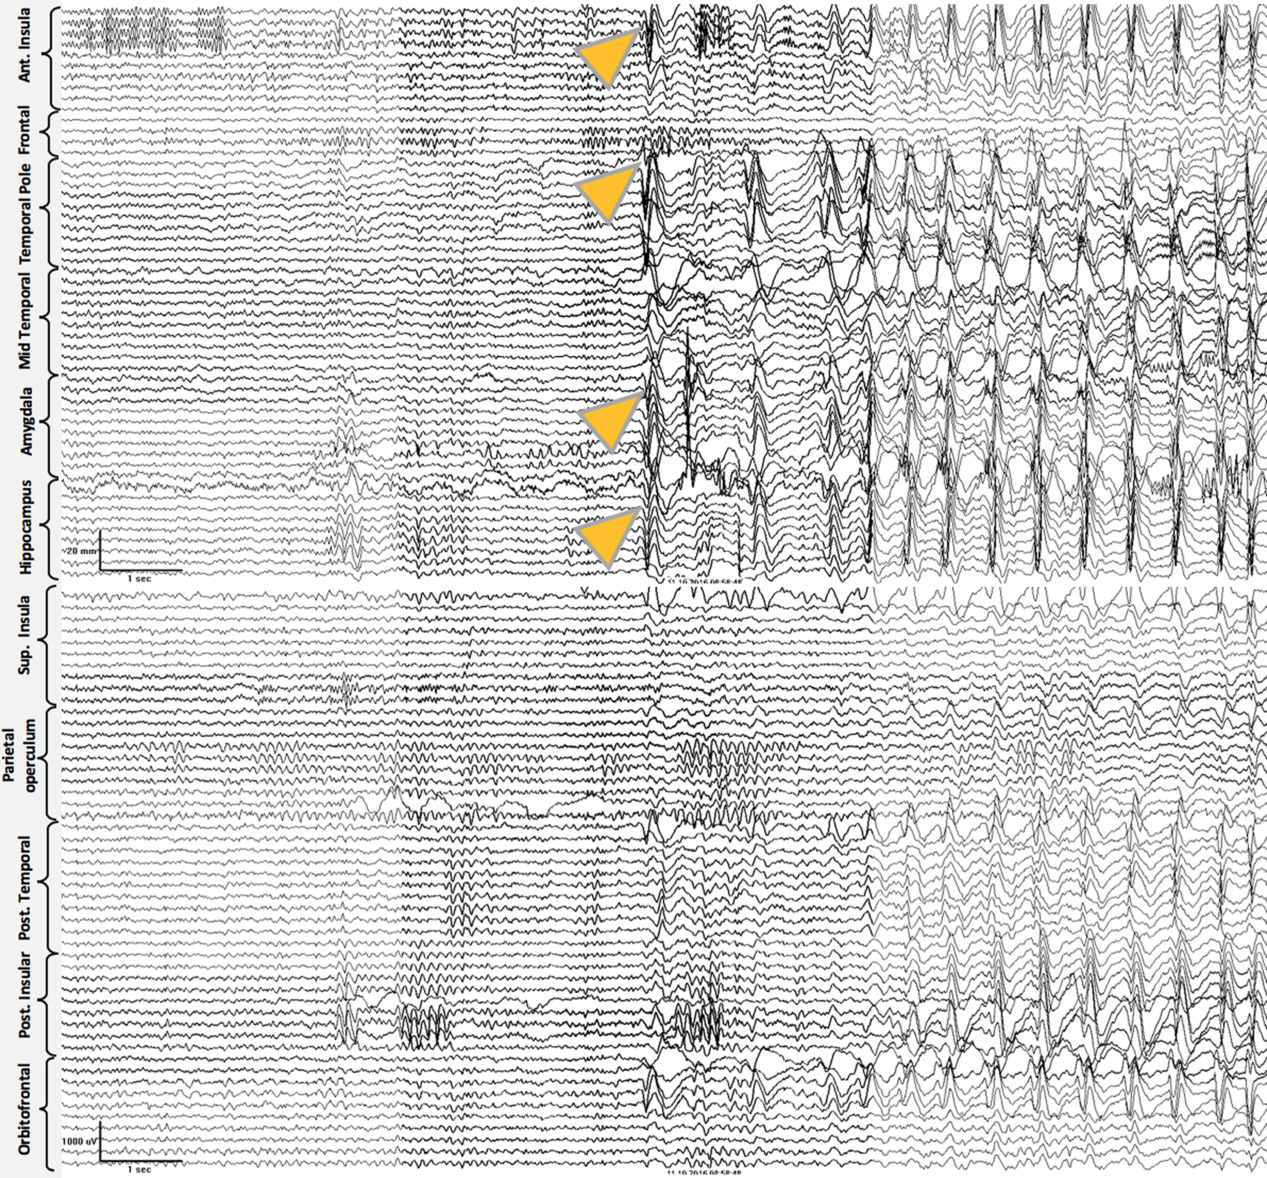

Case 2: Thirty-two-year-old, right-hand dominant male with a history of reflex epilepsy triggered by eating for 5 years. The patient sustained somatosensory seizures with oral automatisms, left head and eye deviation, and postictal right-hand nose wiping. Neuropsychological testing was normal with left language lateralization. MRI revealed hippocampal sulcus remnant cysts on the right. These were considered incidental findings with no abnormal changes in hippocampal volume or signal. PET scan was normal. Scalp EEG showed right temporal seizures extending to the suprasylvian region. The patient was investigated with SEEG, and seven seizures with simultaneous onset in the right hippocampus and inferior insula were recorded (Figure 2). The patient was offered a right ATL with partial resection of the insular cortex. The latter was performed with the aid of neuronavigation, accessing the insula transpially and resecting the tissue that overlapped the active contacts of the depth electrodes involved (Figures 1B, 3A–J and 4A and B). Patient has remained seizure-free since surgery, 1.3 years ago.

Figure 3. Preoperative (superior line images A–D) and postoperative (inferior line images E–H) MRI images for Case 2. (A) Preoperative FLAIR coronal image at the level of the anterior hippocampus . (B) T2-weighted coronal image at the level of anterior hippocampus and posterior section of amygdala. (C) T2-weighted axial image at the level of the amygdala–hippocampus complex. (D) T2-weighted axial image at the level of the insula. (E) T1-weighted sagittal image at the level of the right temporal lobe and insula. (F) Postoperative comparison to image A. (G) Postoperative comparison to image B. (H) Postoperative comparison to image C. (I) Postoperative comparison to image D. (J) Postoperative comparison to image E showing temporal lobectomy and inferior insular resection.